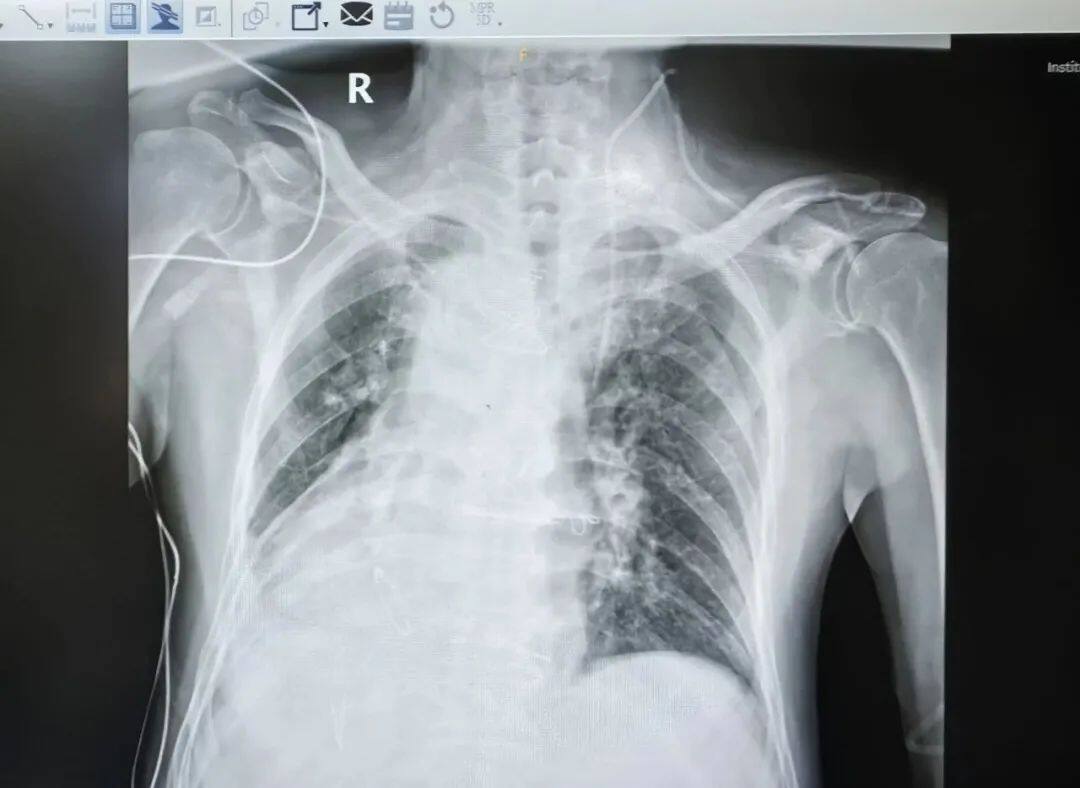

在临床上,专业的术语叫“镜面心”

他是很罕见的“镜面人”。“镜面人”的心脏、肝脏、脾脏、胆等器官的位置与正常人相反,其中心脏位于右侧胸腔,心尖指向右下,又被叫做“镜面心”。